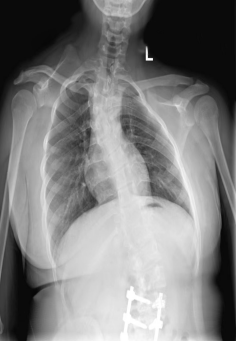

15岁的杨同学(化名)从小被发现两个肩膀高度有差异。但是在小时候,这种差异并不明显,小朋友也没有其他不适,因此家里人并没有过多在意。然而,进入青春期后,随着身体快速发育,这种差异逐渐明显,而且右侧的肩关节活动也有些僵硬,抬胳膊也比较费力,而且正在逐渐加重。这下,家里人也着急了。

又称Sprengel畸形,俗称高低肩,特征是肩胛骨处于较高的位置,是一种影响肩胛骨位置的先天性疾病。其病因尚不清楚,但可能与胚胎期的发育异常和遗传因素有关。